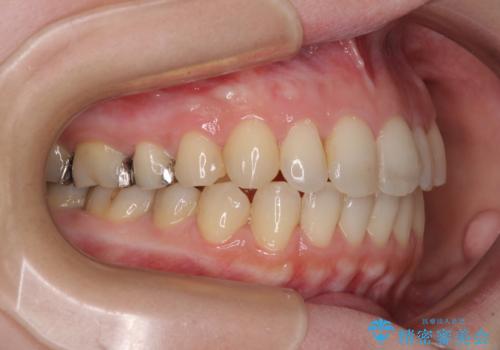

- 治療期間

- 2年6ヶ月

治療途中で出産されたこともあり、当初予定よりも終了までに期間がかかってしまいました。

舌を前方に突出する癖があったため、上下前歯がなかなか接触しなかったことも治療期間が伸びた要因です。